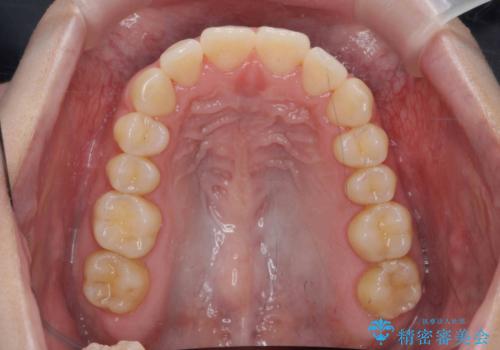

マウスピース 狭窄歯列の改善

- 噛み合わせが深い、笑った時の歯並びの改善を求めて来院されました。

マウスピース型の矯正装置インビザラインを用いた治療を計画します。

狭くなってしまった歯並びを放物線状に並べることで噛み合わせの安定・見た目の改善・ガタつきの改善を達成することができました。